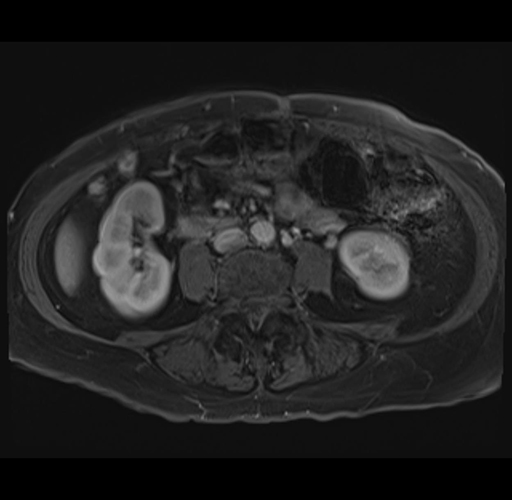

MRI T1